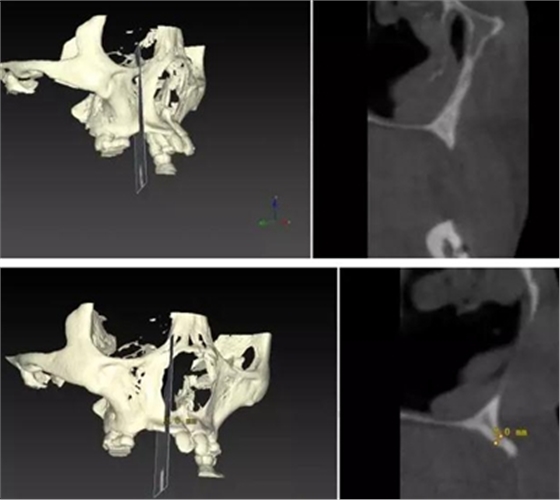

??茩z查:口內(nèi)僅剩16,11,21,26,雙側(cè)上下頜乳牙E滯留,其余恒牙缺失,上下頜骨發(fā)育不足,缺牙區(qū)牙槽嵴呈刃狀,上下頜弓比例協(xié)調(diào)。CBCT顯示:上頜前牙區(qū)牙槽嵴寬度約2-3mm,骨高度約10mm;上頜后牙區(qū)可用牙槽骨高度僅1-2mm,左右側(cè)上頜

竇內(nèi)粘膜有明顯增厚。下頜牙槽骨寬度及高度嚴(yán)重不足,僅存有基骨。